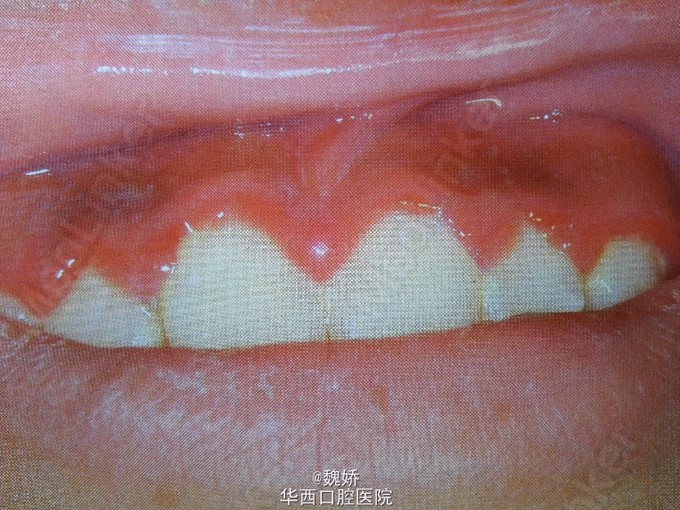

患者,男,2岁。主诉:发烧5天,口腔溃疡3天。5天前患儿开始发烧,最高体温39.5℃,于当地医院输液治疗后体温降低但未完全退烧;3天前患儿哭闹,拒绝进食,家长发现患儿口内长溃疡,牙龈发红。否认系统病史及药物过敏史。

患儿精神状态较差,全口牙龈红肿,上下牙唇颊侧及舌腭侧牙龈、上下唇内侧黏膜,舌前份黏膜均见成簇浅表溃疡;舌苔白厚。